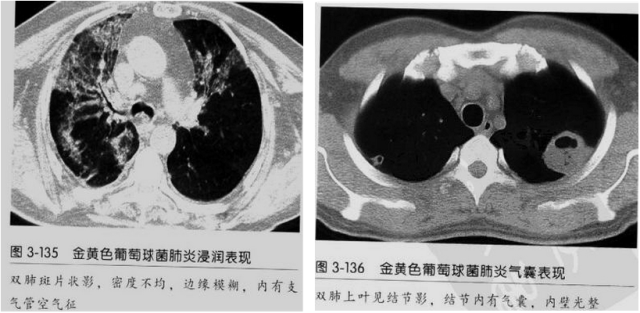

血源性金黄色葡萄球菌性肺炎具有一些临床和影像学特征:

1.起病急,临床症状重;

2.表现多样,多种影像表现可同时出现,如斑片状影、小点状影、结节影、肺气囊等可在CT片上同时见到;

3.病灶比较广泛,多个肺野出现同时受累;

4.容易在短期内出现散在的肺气囊或多发的脓肿病灶;

5.病灶易变,短期内复查CT可见病灶的形态、部位、大小发生变化。

金黄色葡萄球菌肺炎CT征象 来源放射沙龙